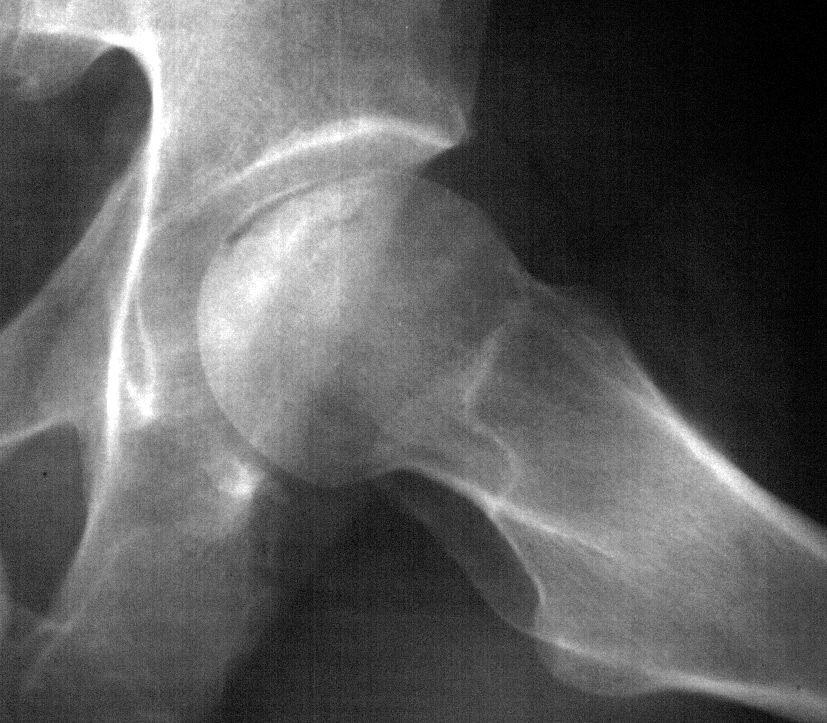

SE APRECIA UNA LINEA DE COLAPSO SUBCONDRAL EL SIGNO DE LA MEDIA LUNARADIOLOGIA NORMAL EL DIAG SE PUEDE REALIZAR POR RESONANCIA MAG

Secuencias Radiológicas

COLAPSO AFECTA LA SUPF SUBCONDRAL PERDIENDO SU MORFOLOGIA NORMAL

LA INCONGRUENCIA ARTICULAR PRODUCE PERDIDA DEL GROSOR DEL CARTILAGO Y CAMBIOS EN EL ACETABULO